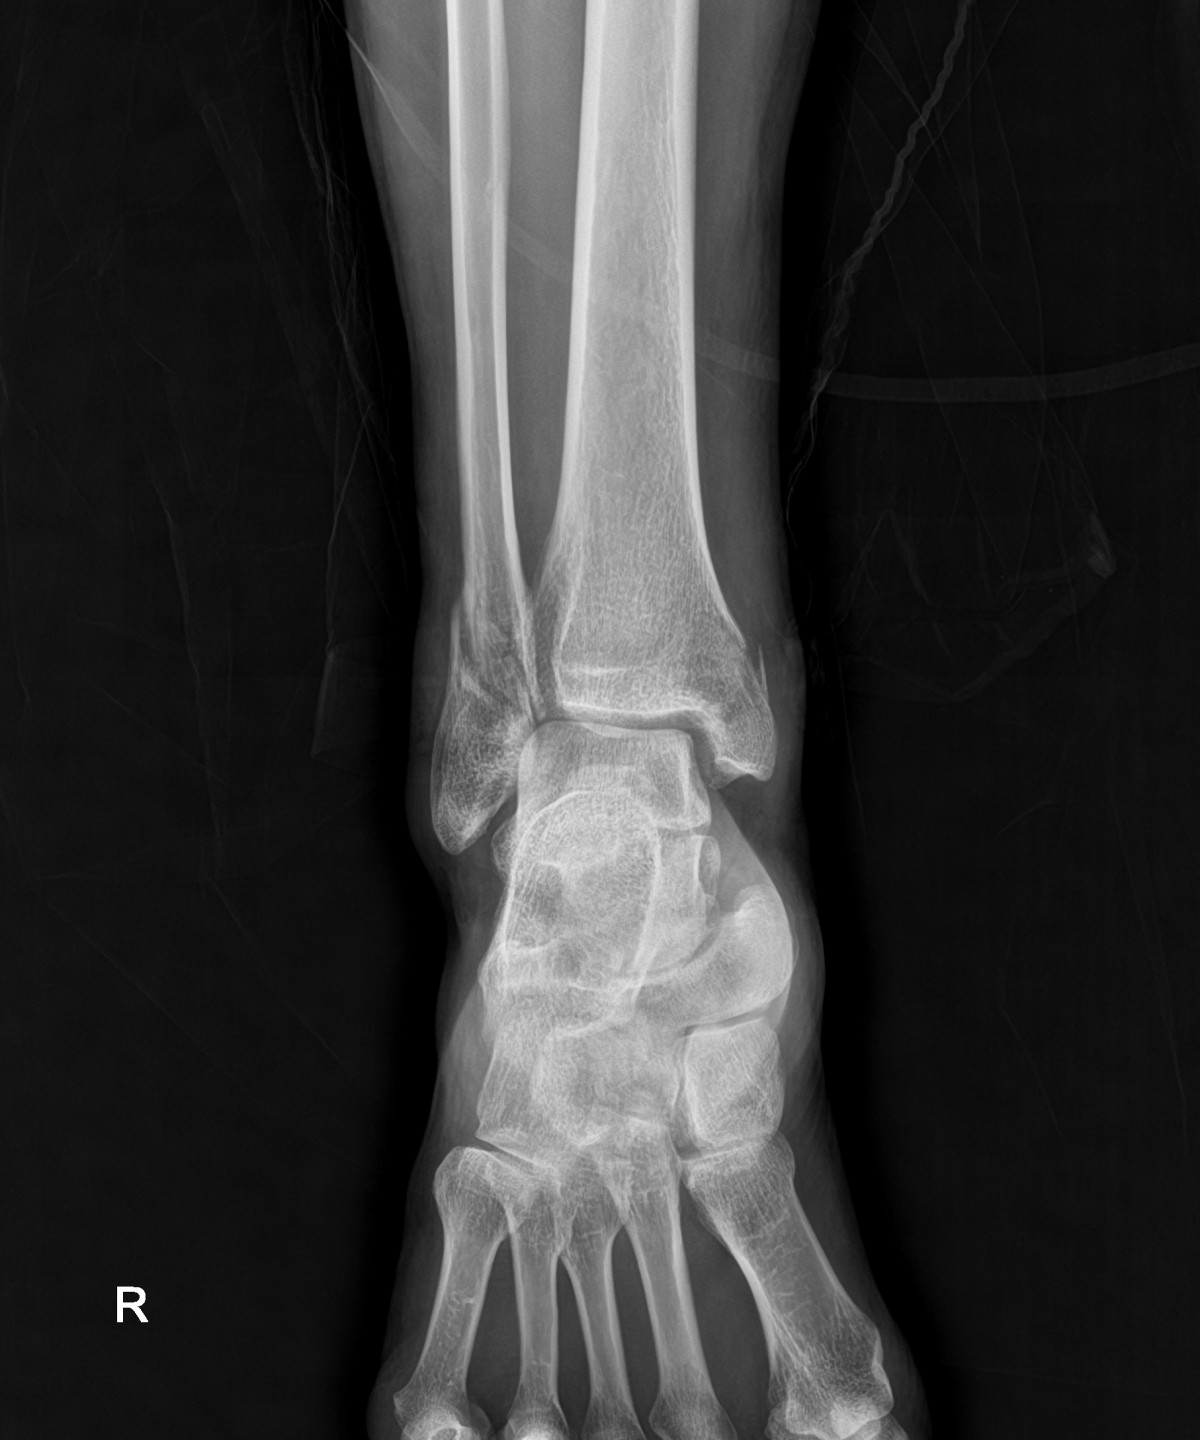

이재상원장님 발목 골절 수술 박근O 환자

dae765e4d9ac96aee867c9d6292d8784_1758002120_9915.jpg